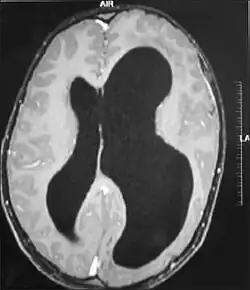

| MRI images showing megalencephaly in four family members who all have unusually large skulls (the family is affected by an autosomal recessive syndrome caused by a KIF7 mutation that induces multiple epiphyseal dysplasia)[1] | |